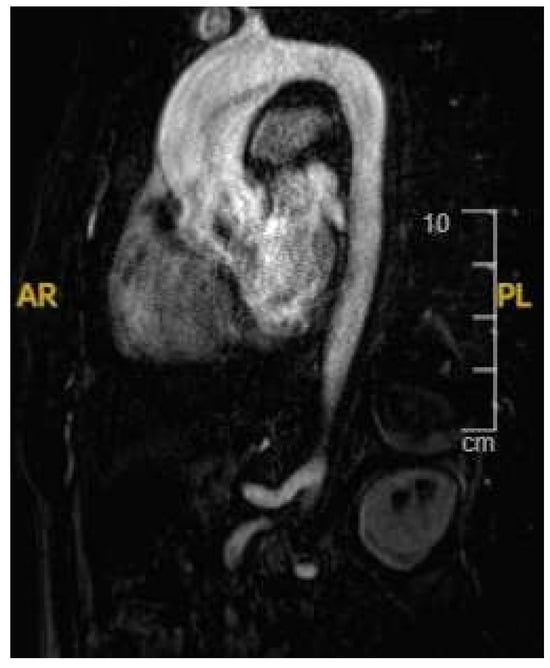

The cardiac MRI acquisition should include standard long-axis and short-axis cine stacks, phase-contrast sequences of the aortic and pulmonary root, and post-contrast sequences [105,106]. These sequences provide a comprehensive morpho-functional evaluation of the mitral valve and subvalvular apparatus, including localising prolapsing segment/s, prolapse severity, leaflet thickness, papillary muscle anatomy, and MAD and MR quantification. CMR has been found to be more sensitive to identifying MAD compared to transoesophageal echocardiography and transthoracic echocardiography [107]. Additionally, cardiac MRI aids in identifying anterior MVP, as it directly correlates with non-ischaemic fibrosis of the papillary muscles and LV inferolateral basal segment (Figure 9). Both of these are linked to prolapsed leaflets and annulus hypermobility [108]. In cases of minimal MR, cardiac MRI may reveal a disproportionate LV remodelling and fibrosis associated with malignant arrhythmias, facilitating the identification of athletes at elevated risk [104]. Further, there is emerging evidence of the role of cardiac MRI in identifying myocardial ECV through T1 mapping. Studies have demonstrated that ECV is increased in MVP patients with MAD compared to those without MAD and MR or isolated MVP [108]. Moreover, MVP patients who have sustained out-of-hospital cardiac arrest exhibit a higher ECV and LGE [30].

Figure 9. A 42 year old Caucasian male, engaging in power sport (recreational) for 20 years, presented with a profound drop in exercise tolerance. Murmur heard on physical examination. T-wave inversion in the inferior leads noted. Supraventricular arrhythmias during an exercise test. Mitral valve (MV) prolapse with moderate regurgitation noted on echocardiogram. Cardiac MRI showed a dilated LV, an LV ejection fraction of 58%, and mitral annular disjunction (arrow) (A). There was prolapse of the posterior MV leaflet with moderate regurgitation (B). Post-contrast imaging identified a subepicardial scar in the lateral wall (arrow) (C,D), consistent with a diagnosis of malignant MV prolapse. He was subsequently referred for MV surgery.

Athletes with MVP in the absence of high-risk features are often cleared for competition. The presence of any of the high-risk features should prompt referral to sport cardiology experts, with cases adjudicated on a case-by-case basis in a shared-decision approach [9,10].